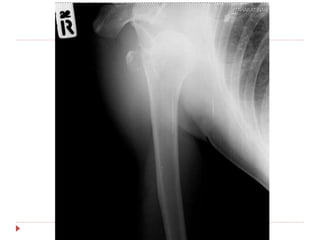

 Film right shoulder AP , transcapular

 Film right humerous AP , lateral

Right anterior shoulder dislocation

with avulsion fracture right greater

tuberosity

investigation  Film rightshoulder AP , transcapular  Film right humerous AP , lateral

Imp : Right anteriorshoulder dislocation with avulsion fracture right greater tuberosity